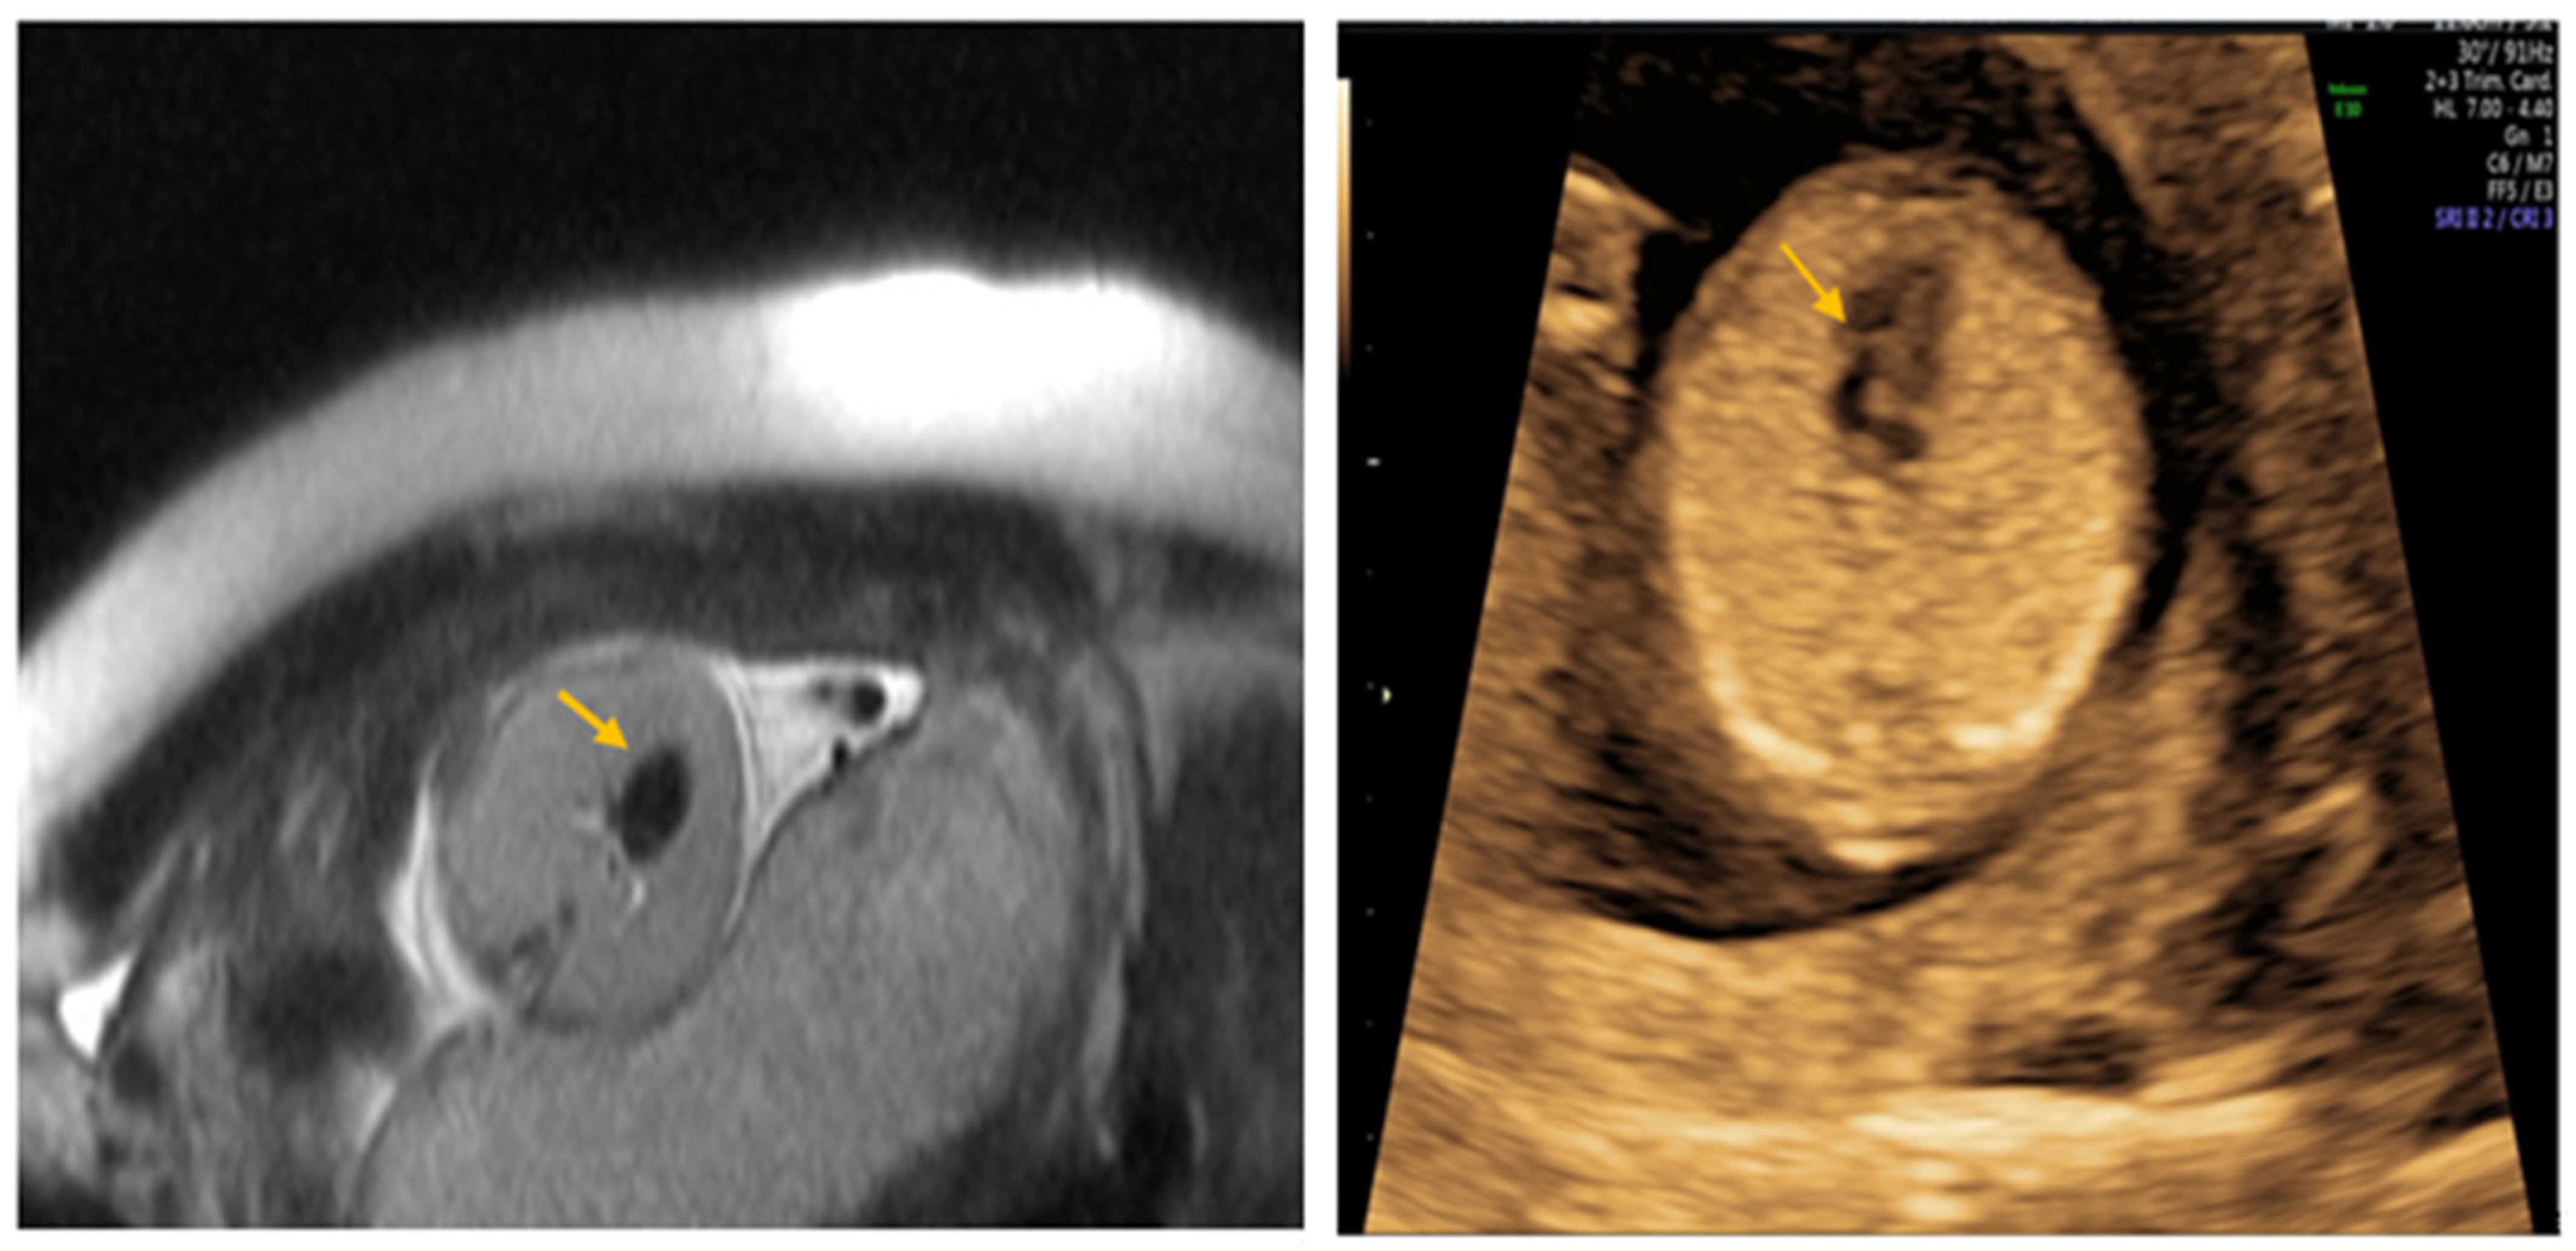

2. Case Report